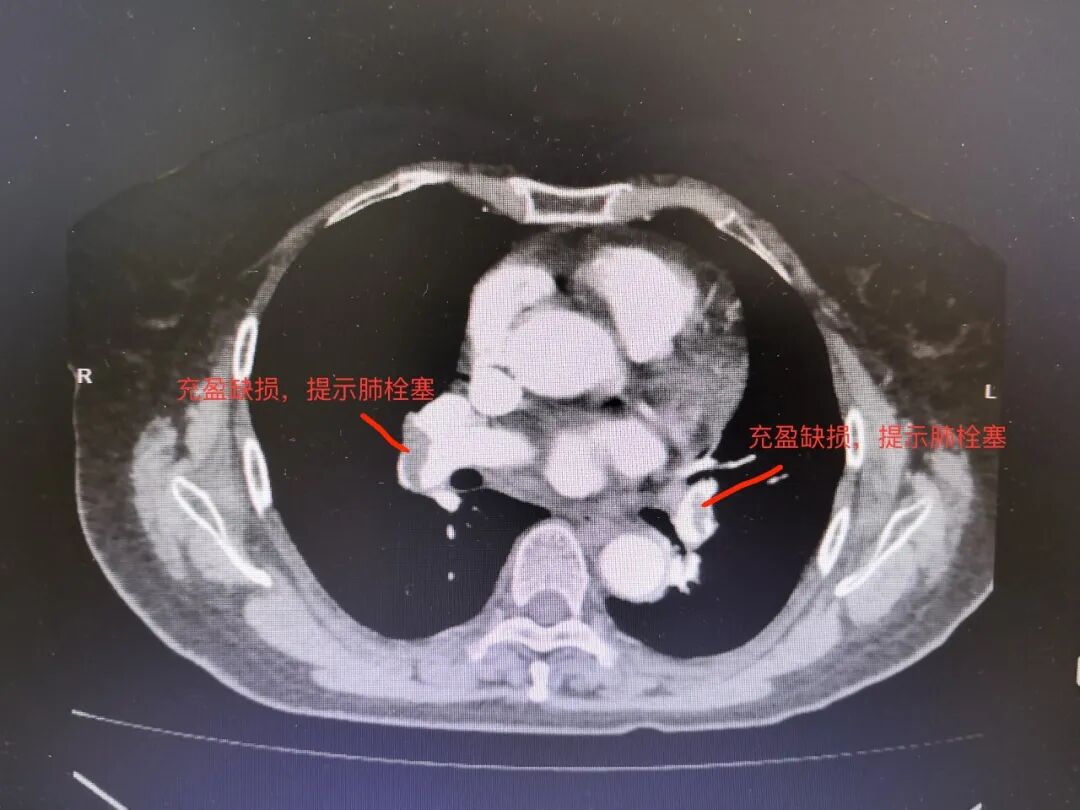

随后的肺动脉CTA检查揭示了真相——左右肺动脉均发现栓塞。原来,困扰徐阿姨一年的胸闷,竟是肺栓塞这个“隐形杀手”在作祟。